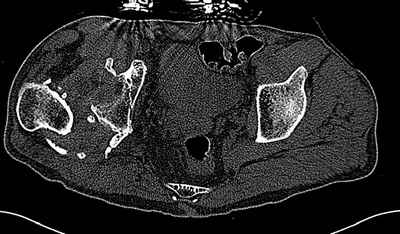

На последнем срезе КТ задний край практически отсутсвует по сравнения со здоровой стороной. Разумеется, что это плоскостное изображение, но головка вывихнулась не только в плоскостную щель захваченную на КТ. Если вы считаете, что удастся установить туда чашку даже низкопрофильную, остается пожелать вам успехов. Но перед этим можно смоделировать установку чашки на скиаграммах КТ.

За пожелание успехов - спасибо, думаю это пригодится, не очень понял про плоскостную щель, специально предоставил срезы на уровне свода - он цел, дефект заднего края ниже, за счет заглубления он будет еще меньше, по данным 3d - должно получиться.

Решение по ВВ придется принимать по месту.... Сумеете "подрыться" и получить хорошее покрытие чашки (+2 винта об-но) - хорошо, если нет -

костная аутопластика из головки.